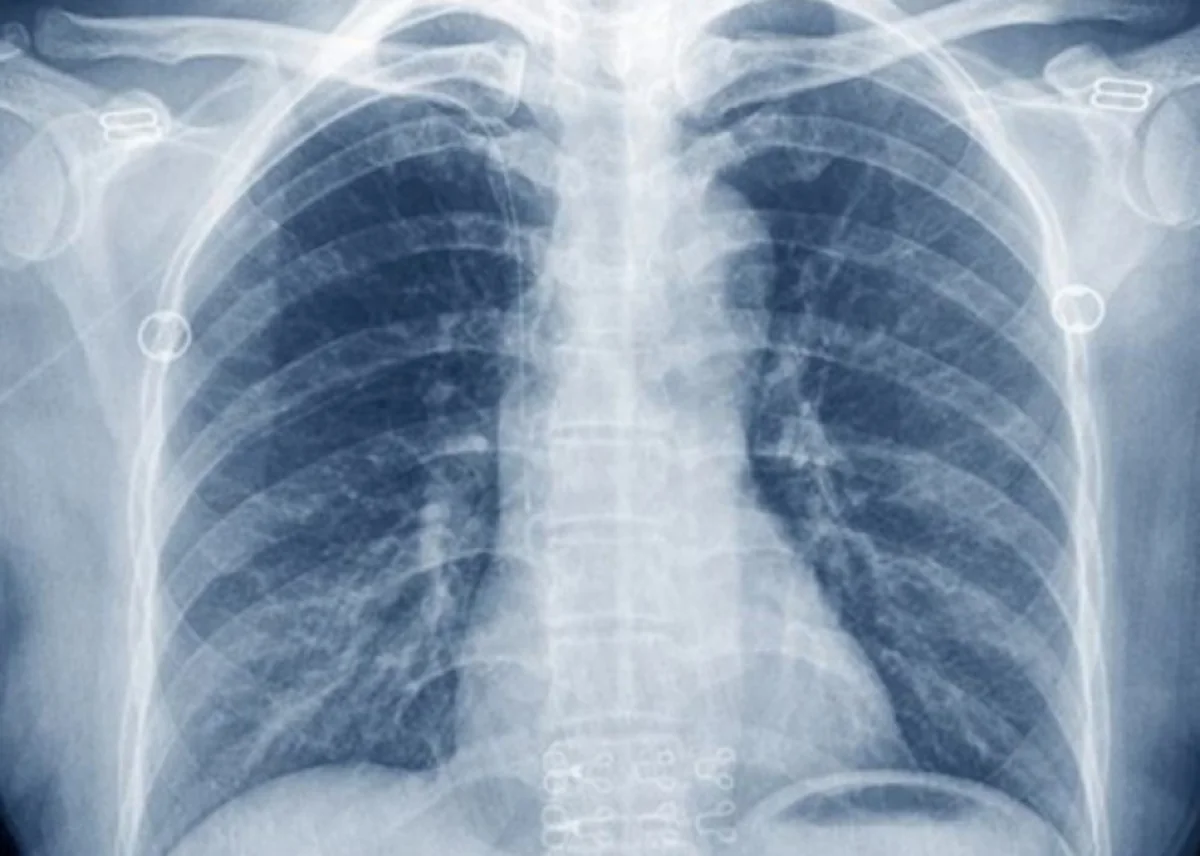

Специалисты международного Фонда рака легких раскрыли неожиданный признак онкологического заболевания.

Как передает Report со ссылкой на издание Express, по их словам, необъяснимые охриплость и ослабление голоса могут свидетельствовать о наличии рака легких. Специалисты пояснили, что изменения голоса могут быть вызваны раковой опухолью, которая давит на гортанный нерв в грудной клетке.

Отмечается, что изменения в голосе чаще являются признаком рака правого легкого, чем левого. При появлении подобных симптом специалисты рекомендуют немедленно обратиться врачу.